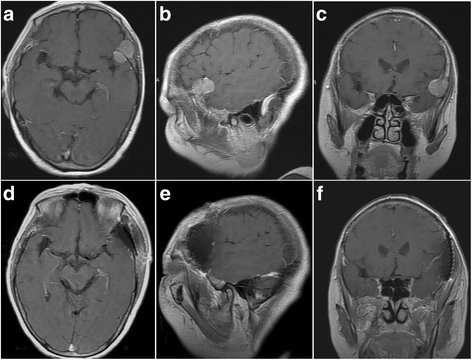

A 63-year-old female patient with an atypical meningioma was treated in our department with a complaint of dizziness for 1 month. She had fallen down accidentally while riding and sustained a chest contusion without head injury 1 month earlier. The dizziness appeared thereafter. Cranial computed tomography (CT) showed a slightly hypertensive lesion in the lower inner panel of the left temporal bone and an expansive local skull plate, including soft tissue density, leading to the consideration of an intracranial mass (Fig. 1). The patient reported no headache, nausea, hemiplegia, aphasia, or limb convulsions since the onset of dizziness. Additional relevant examinations were conducted after admission, and a physical examination showed no positive pathological signs. A cranial dual-source and thin-layer CT scan revealed local expansive lesions in the left temporal bone with invasion into the skull and osteolytic lesions. Based on 3-dimensional skull imaging, a postoperative skull defect was designed and a 3-dimensional artificial skull was created for first-stage reconstruction. Magnetic resonance imaging (MRI) revealed an area of frontotemporal, subdural, and intracranial homogeneous enhancement on the left side with an approximate diameter of 4 cm, with no obvious dural tail sign (Fig. 2). The tumor was divided into inner and outer parts by the inner skull plate.

The tumor was removed via a modified pterional approach under general anesthesia. The skin flap was turned to the base of the skull, and the local skull bulge, measuring 2 cm × 2 cm, was visible. Next, a 4-cm × 4-cm bone flap, centered on the skull bulge, was resected to reveal tumor protrusion to the inner side of the skull. Although the tumor had not adhered to the dura mater, local tumor invasion into the dura mater was visible. Having incised the dural mater, the subdural part of the tumor measured approximately 2 cm × 2 cm and had compressed the brain lobe in a convex manner. The tumor boundary was clear without obvious adhesions to brain tissues, and the en block resection of the tumor along with the dural pedicle was performed to achieve a Simpson grade I resection (Fig. 3). Following artificial dura repair, the skull was repaired using the preoperatively designed artificial titanium skull.

The surgical procedure was as follows: the skin flap was opened to reveal the local skull bulge through a left frontotemporal incision (a and b). c After removing the invaded skull, the dura mater and skull were not found to adhere to each other. d The dura mater was incised to reveal the tumor, and the base of the tumor was found to adhere to the dura mater. Therefore, the tumor and dura mater were resected (e), and first-stage repair was performed (f)